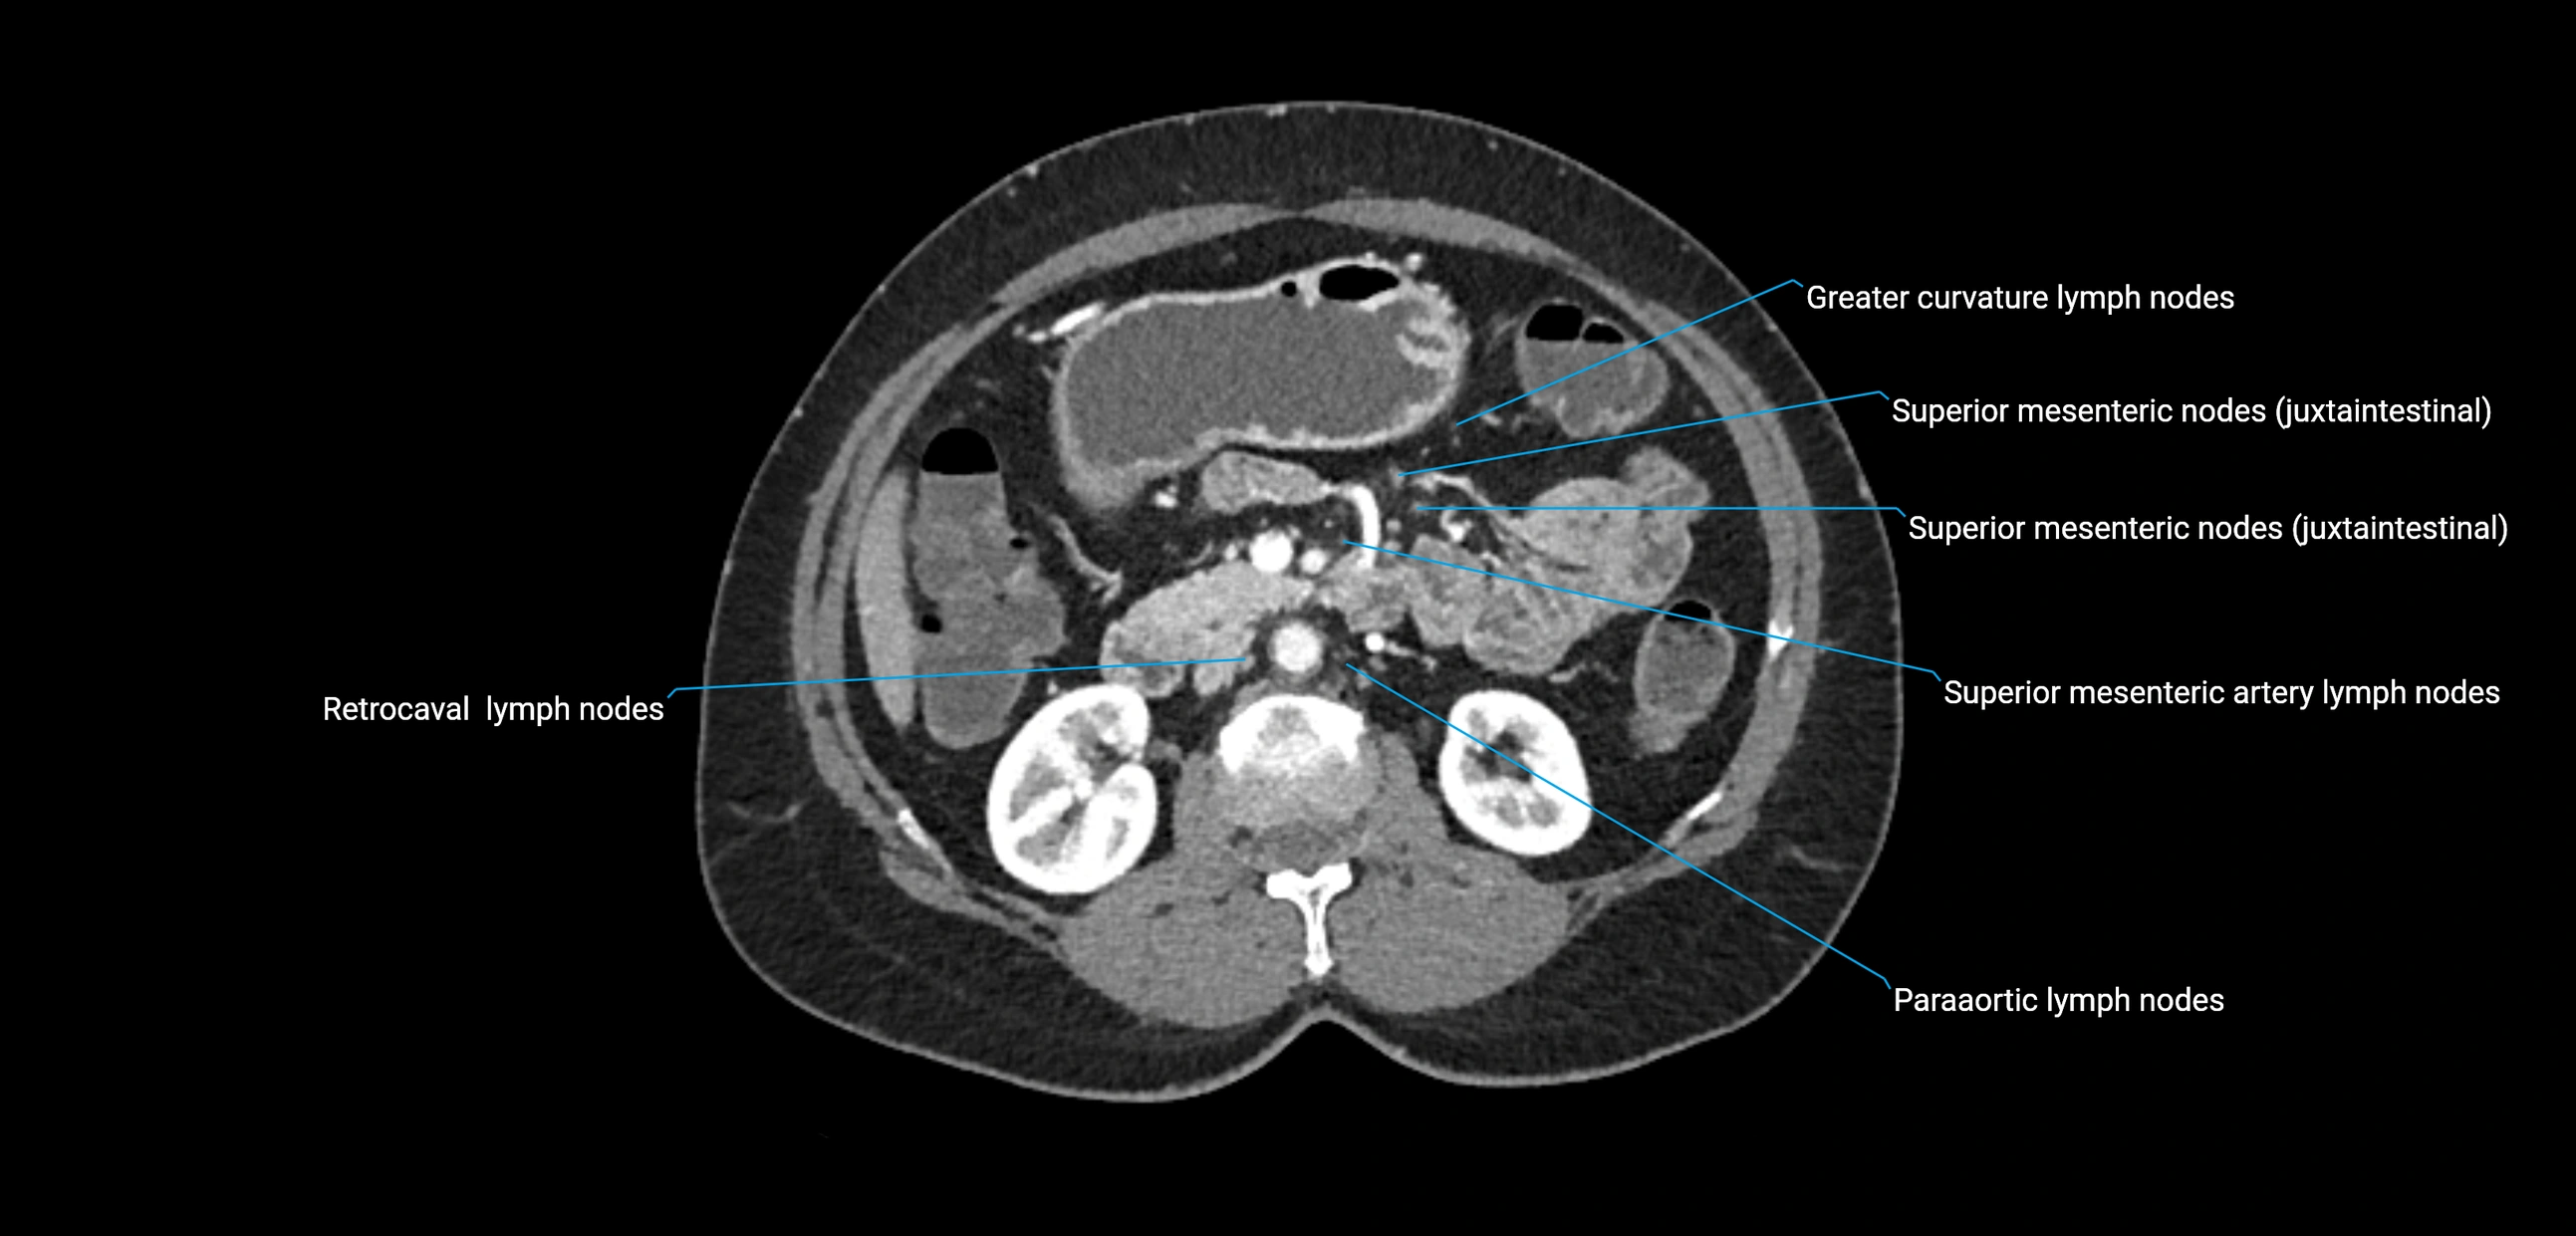

CT image

image